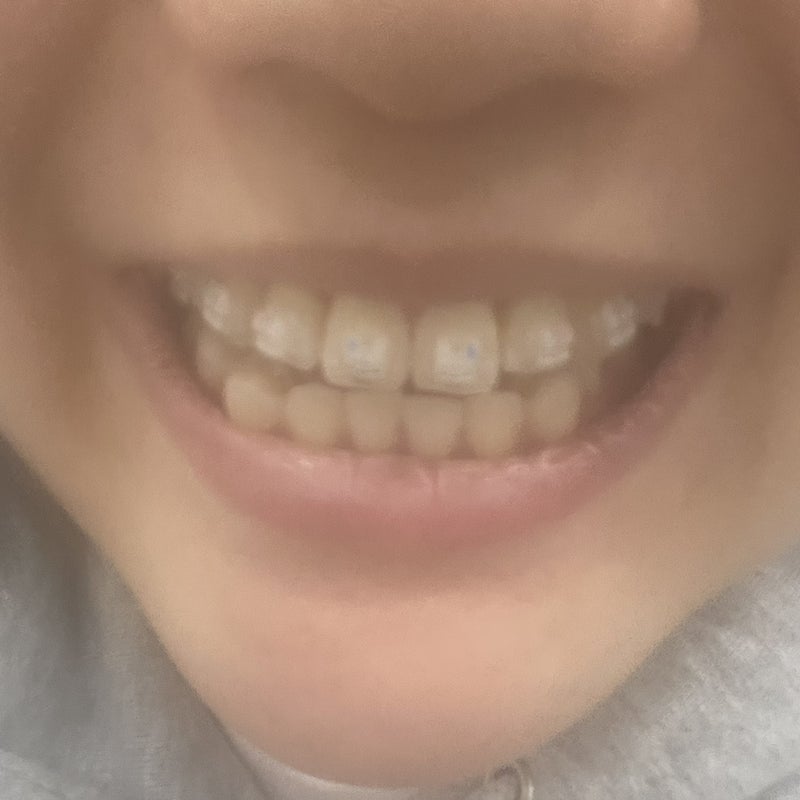

上の歯は矯正してたけど

保持装置が切れて少しずれた

下の歯も下の歯を見ると、あまり歪んでいる方ではないようだが

上の歯に装置を付けた時!!!!!

すごく変な感じでwww

ちょっとおかしかったwww

上下の装置を全部つけてから..

波打つワイヤー······

私はブラケット矯正(クリッピーシー)で進行したが